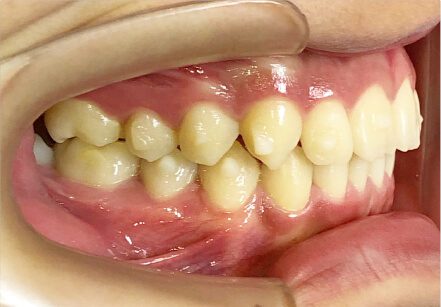

叢生の症例

10歳

/

女性

相談内容

スペース不足

カウンセリング・診断結果

myoからの移行。スペース不足のためインビザライン開始。

治療内容・方法

全額アライナー矯正

術後の経過・現在の様子

クリアライナー使用

治療のリスク

痛み・歯根吸収・歯肉退縮・虫歯・後戻り

費用・治療期間

(インビザのみ)385,000円、1年2ヶ月 + myo3年4ヶ月

トレーニングなど